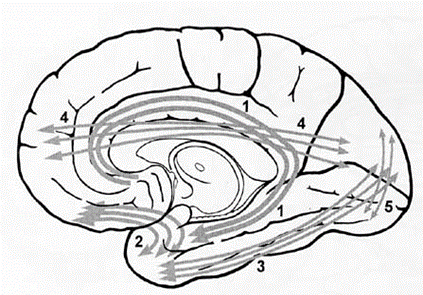

연합섬유는 같은 쪽 cerebral cortex 내에서 여러 부분을 연결하는 섬유를 가리킨다. 연결 시키는 섬유다발의 형태가 활이 휘어진 것 같은 모양이기 때문에 연합섬유의 다발을 대뇌궁상섬유(cerebral arcuate fiber)라고도 한다.

짧은 연합섬유(short association fiber)는 인접한 이랑의 피질을 연결시 키는 역할을 하며 고랑의 장축에 대해 가로 방향으로 배열되어 있다. 긴 연합섬 유(long association fiber)는 다른 대뇌엽 사이, 또는 비교적 멀리 떨어진 같은 대뇌엽의 피질을 같은 쪽 대뇌반구에서 연결시켜 주는 역할을 한다.

긴 연합섬유에는 갈고리다발(uncinate fasciculus), 하세로 다발(inferior longitudinal fasciculus), 상세로 다발(superior longitudinal fasciculus, 궁상다발 arcuate fasciculus), 대상다발(cingulum, 대상 속), and inferior occipitofrontal fasciculus), 수 직후두다발(perpendicular occipital fasciculus) 등이 있다.